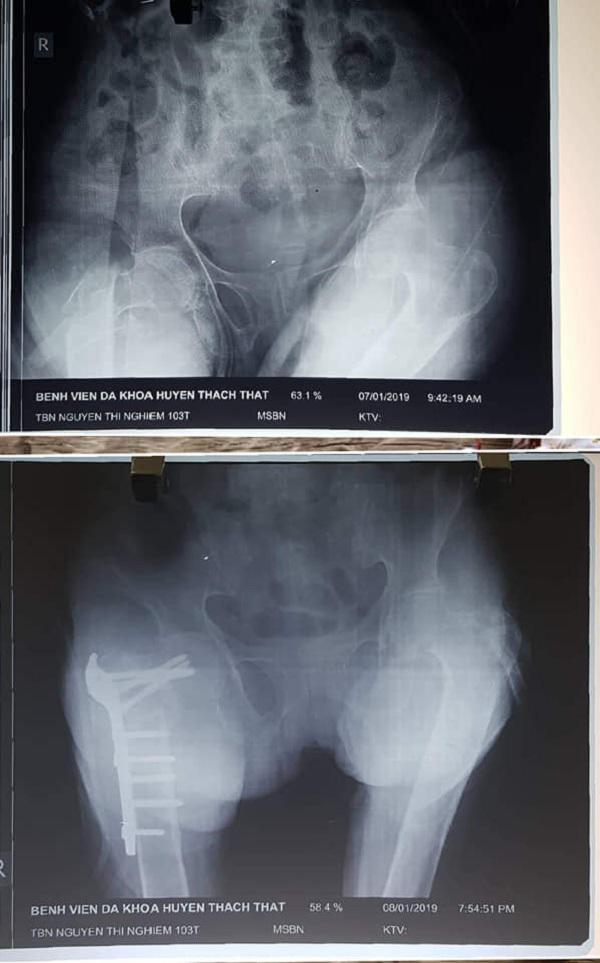

Hình ảnh chấn thương của cụ Nghiêm trước và sau khi được phẫu thuật.

Kết quả chụp chiếu cho thấy, cụ Nghiêm bị gãy xương đùi phải. Dù gia đình đã xin được mổ, nhưng do tuổi quá cao, kèm theo nhiều bệnh tật của tuổi già, tiềm ẩn nhiều rủi do vì thế các bệnh viện đều chỉ định bó bột và cho xuất viện.

Sau gần 4 giờ hồi sức và phẫu thuật ca mổ đã diễn ra thành công vào lúc 19h15 phút ngày 8/1/2019. “Ca này không chỉ là mổ khó vì chân của bệnh nhân đã biến dạng, bị teo... Sau mổ bệnh nhân còn suy thận, suy tim, tràn dịch tràn khí màng phổi nhưng bệnh viện đã phối hợp các chuyên khoa điều trị thành công được”, BS Kiên cho hay.